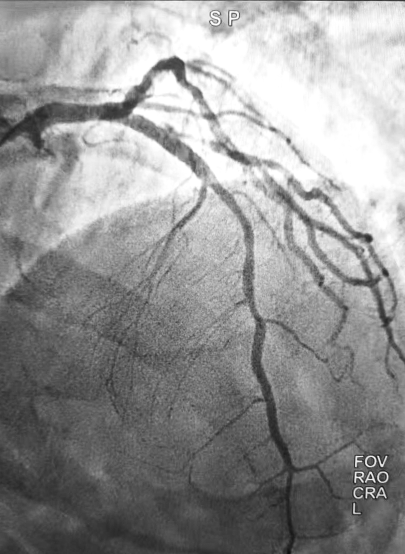

面对复杂的血管病变,手术团队沉着应对,凭借丰富的介入治疗经验,精准操作:先通过球囊扩张技术疏通闭塞血管,再成功植入药物支架。再次造影显示,支架内无残余狭窄,闭塞血管被成功打通,血流恢复至TIMI 3级(正常血流灌注),手术达到预期效果。

(▲治疗后)